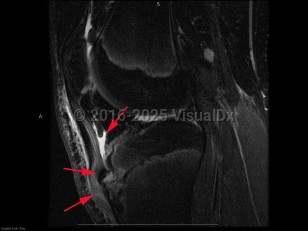

Osgood-Schlatter disease in Adult

Causes / typical injury mechanism: Osgood-Schlatter disease (OS), also known as juvenile osteochondrosis of the tibial tubercle, is a disorder involving inflammation, pain, and swelling of the tibial tuberosity. It is most common in young adolescents, particularly those regularly involved in athletics. OS typically occurs soon after a growth spurt. Symptoms last for 12-18 months, often resolving spontaneously with the closure of the physeal plate of the tibia, although there is a small subset of patients who experience pain after skeletal maturation.

Pathophysiology: The underlying pathophysiology of OS is poorly understood. Its association with sports participation has led to the hypothesis that it is related to repeated small injuries to the developing knee associated with traction from the patellar tendon.